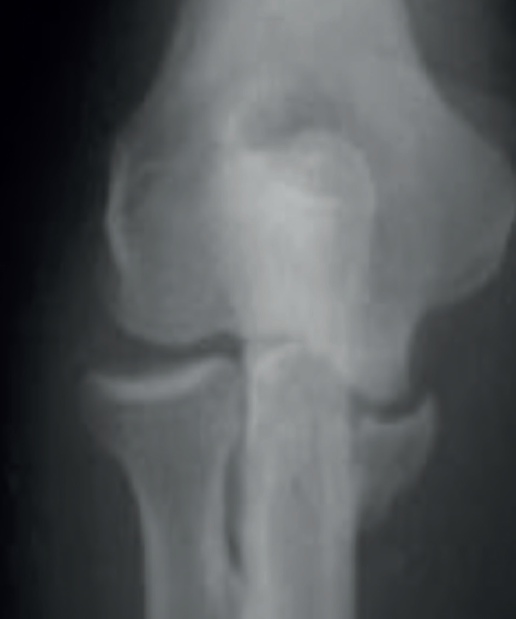

El siguiente patrón de inestabilidad tiene lugar tras una caída hacia atrás con el brazo extendido y provoca una inestabilidad en varo posteromedial. Se lesiona el LCL y se fractura la carilla anteromedial de la coronoides. En este tipo de lesiones, la cabeza radial típicamente no está fracturada.

Este tipo de lesiones se puede confundir con una fractura-luxación de Monteggia-Bado I. La diferencia es que no se ve afectada la articulación radiocubital proximal y los ligamentos colaterales medial y lateral permanecen anclados al fragmento distal del cúbito (Figuras 1, 2 y 3).